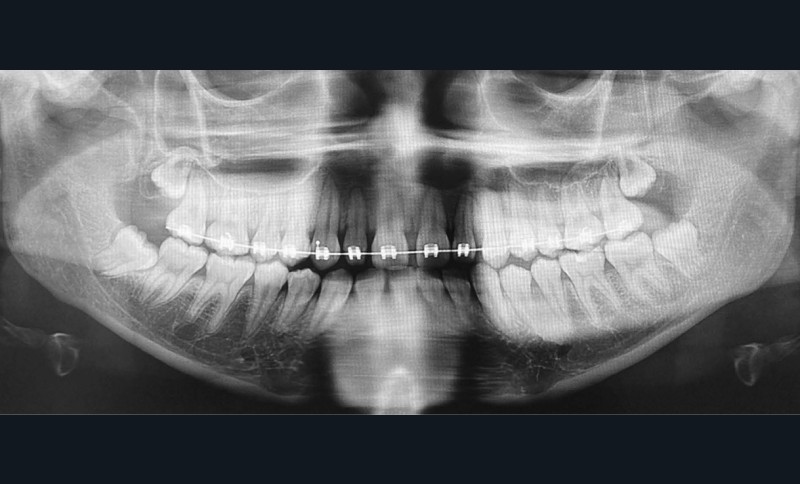

La radiographie panoramique permet de confirmer l’inclusion de la 23, apicale aux dents 21 et 22, ainsi que la présence d’un odontome en apical de la 63. Ces éléments nécessitent la réalisation d’un CBCT.

Le CBCT révèle une position très apicale de la 23. L’apex est fermé.